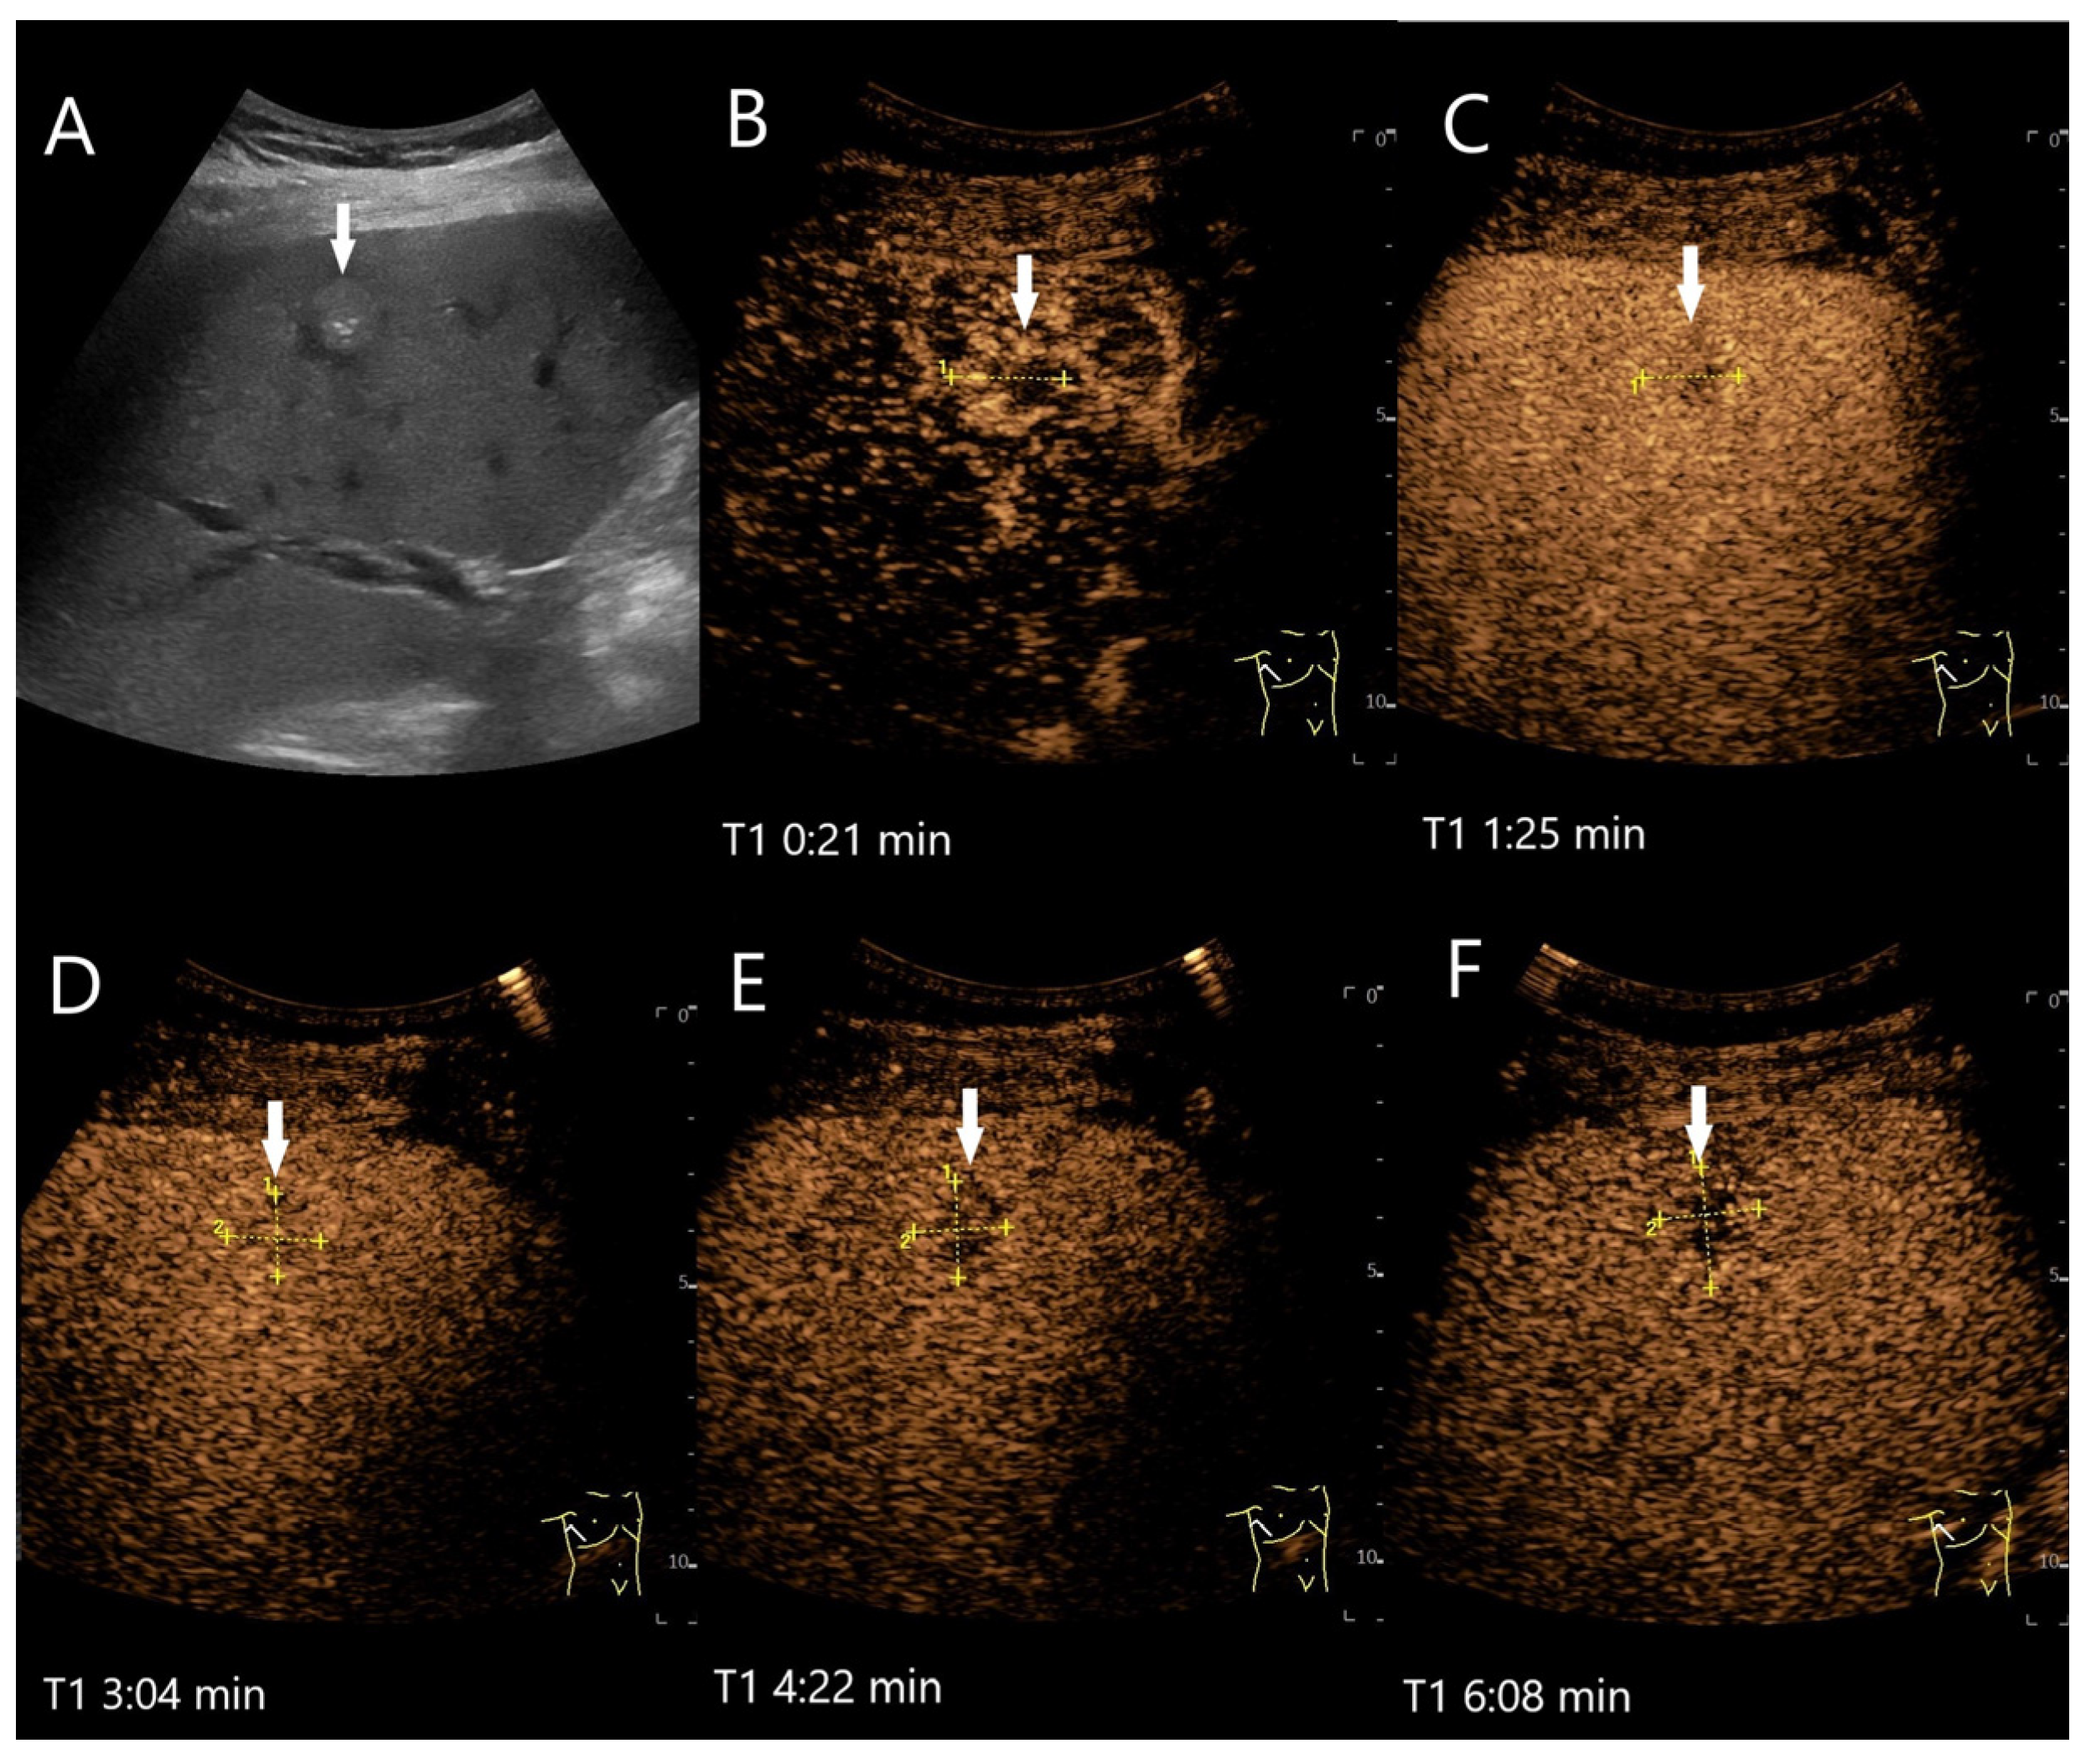

| Hemangioma | Hyperechoic, beyond liver veins, hypoechoic in steatosis and with shunts. | Peripheral globular enhancement, centripetal filling. Rapid homogeneous filling in shunt hemangiomas. | Hyperenhancement and isoenhancement. | Permanent video loops with destruction of the UCA bubbles and slow refill. Fibrosis. |